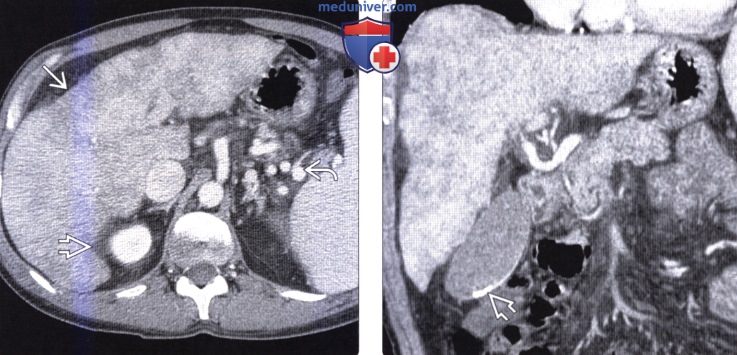

Методы динамического контрастирования печени на МРТ

Раздел: Снимки-подсказки